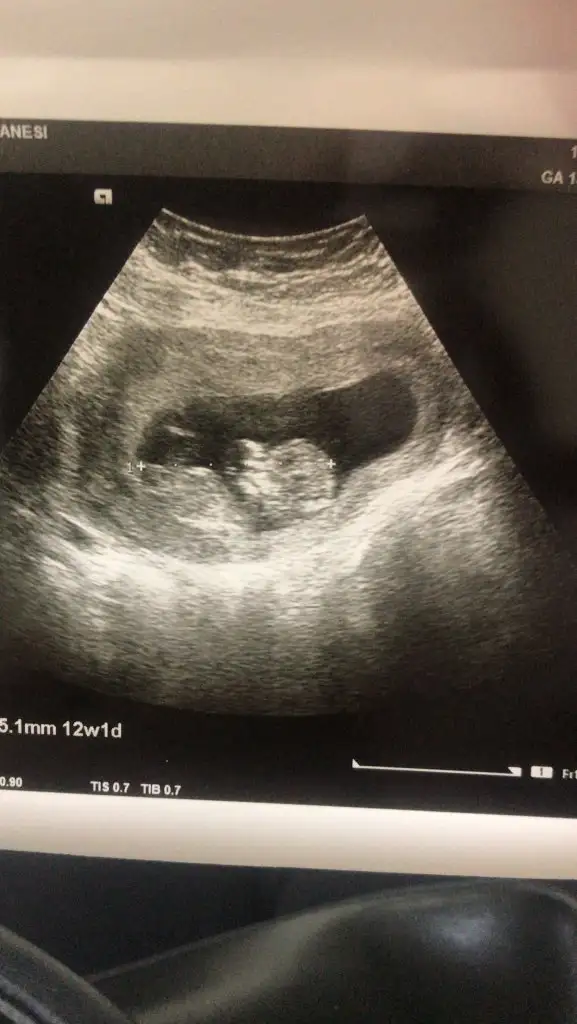

Kız gibi tabi en iyi 11 12 13 haftalar olmalıMerhaba,Ikra meyra bana da tahminde bulunabilir misiniz? Ultrason karından çekilmişti. Teşekkür ederim

Çok teşekkür ederim. 12+3 te randevum var. O zamanda gönderirim. SevgilerKız gibi tabi en iyi 11 12 13 haftalar olmalı

Net değil ama sanki kız gibi geldi banaMerhaba bana da tahminde bulunabilir misiniz 12+1